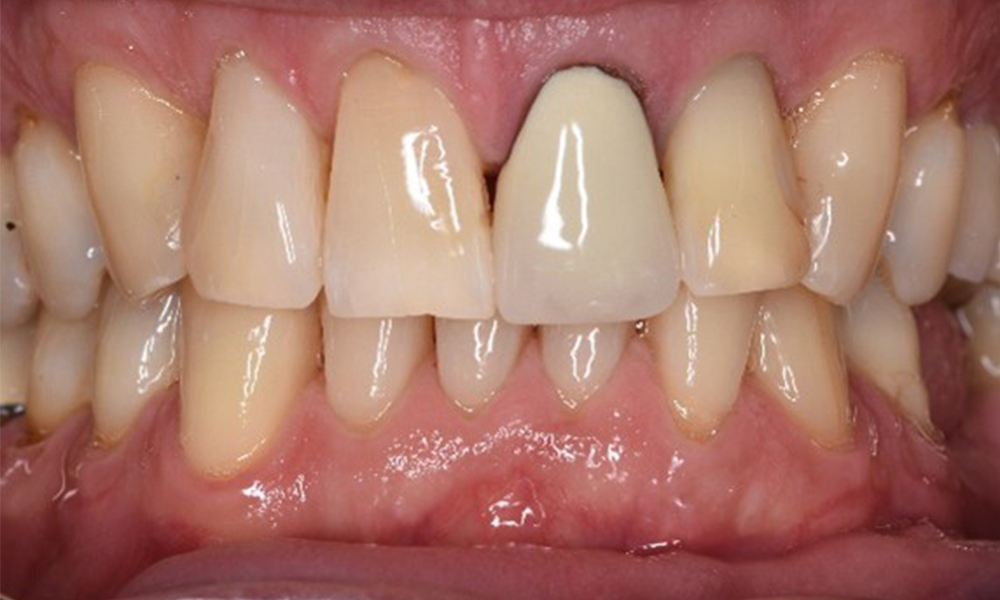

In terms of instruments, specific procedures are required for use with implants. In order to preserve the surface of the implant while cleaning it effectively, it is essential to choose suitable powders and instruments, such as the targeted use of air polishing devices with special periodontal tips. Which powder is most suitable can be determined according to the needs and risk. For example, in addition to the appropriate degree of abrasion, dietary requirements (including sugar-free, low-salt) may also be taken into account.

No adjuvants are indicated for the patient in this case. The use of a fluoridated toothpaste is recommended for prevention of caries.

On the basis of the stable periodontal and peri-implant situation, it is recommended that the patient should have check-ups every six months.